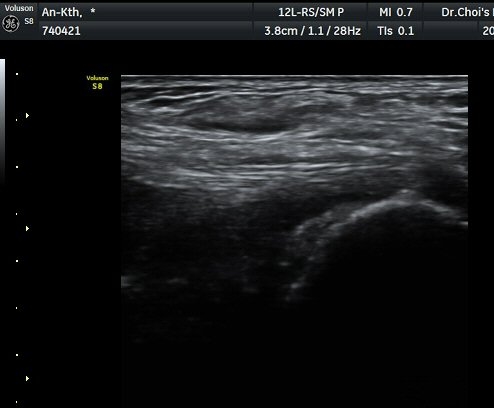

ÃÊÀ½ÆÄ ¼Ò°ß

¹ß¸ñ ³»Ãø Ⱦ´Ü¸é°Ë»ç¿¡¼­ ±ä¾öÁö±¼°î°Ç(FHL)ÀÇ ºÎÁ¾°ú °Ç ÁÖÀ§ ¼ö¾×Àú·ù°¡

°üÂûµÈ´Ù(±×¸² 1, 2, 3). ±ä¾öÀÚ±¼°î°Ç Á¾´Ü¸é°Ë»ç¿¡¼­ ±ä¾öÁö±¼°î°ÇÀÇ ºÎÁ¾°ú